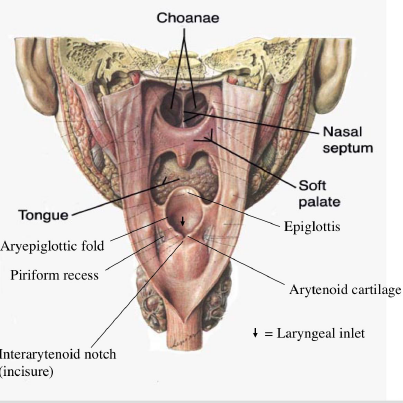

Laryngopharynx

Sensor:CN X

- Epiglottis

- Choana 後鼻孔

- Piriform recess

- (medial) larynx;

- (lateral) thyroid cartilage

- (posterior) Inf. pharyngeal constrictor m.

Muscle

外部

-

pharyngeal constrictor

- CN X (Pharyngeal plexus) 控制